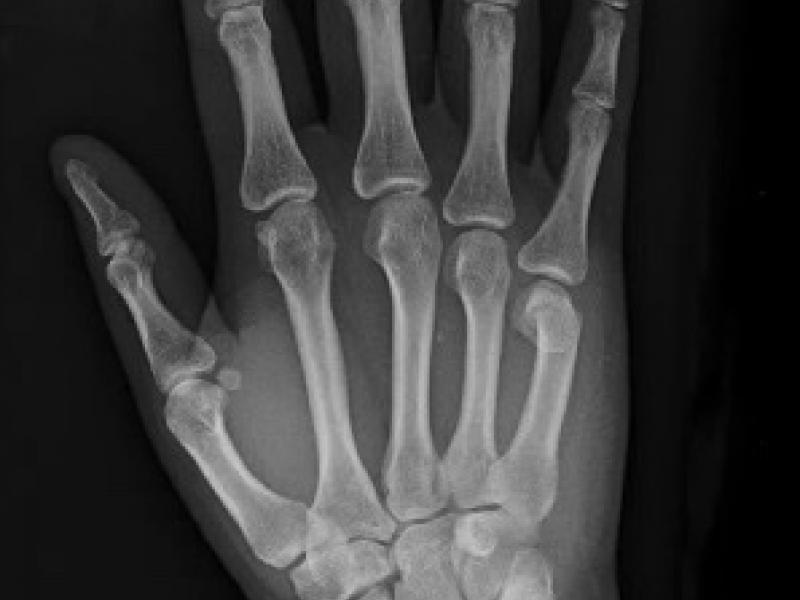

A 63 you male presents with back pain and lower extremity